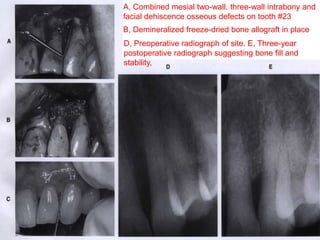

A, Combined mesial two-wall, three-wall intrabony and

facial dehiscence osseous defects on tooth #23

B, Demineralized freeze-dried bone allograft in place

D, Preoperative radiograph of site. E, Three-year

postoperative radiograph suggesting bone fill and

stability,